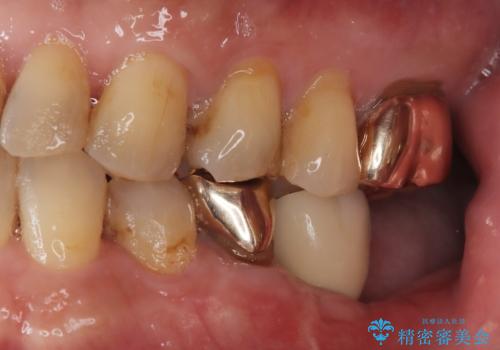

【インプラント】銀歯が取れて歯ごと折れた

- 「奥歯の銀歯が取れた」を主訴に来院された患者さんです。

診査診断を行った結果、歯が折れた位置が深く、虫歯にもなっていたため抜歯後、インプラントで治療を行いました。

残根状態の歯を抜歯後、抜歯窩の治癒を待ちインプラントを埋入しています。